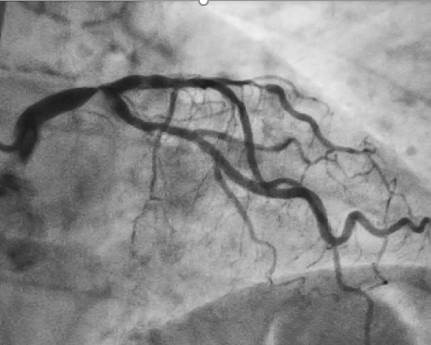

O diagnóstico de doença coronariana no tronco da coronária esquerda (TCE) pode causar preocupação, mas é importante saber que existem tratamentos modernos e eficazes disponíveis. Este texto visa esclarecer suas dúvidas sobre o tratamento percutâneo (angioplastia), uma opção terapêutica que tem mostrado excelentes resultados em casos selecionados

O tronco da coronária esquerda é um vaso sanguíneo crucial que fornece aproximadamente 75% do sangue para o coração. Quando existe obstrução significativa neste vaso, o tratamento adequado é fundamental para preservar a vida e qualidade de vida do paciente.